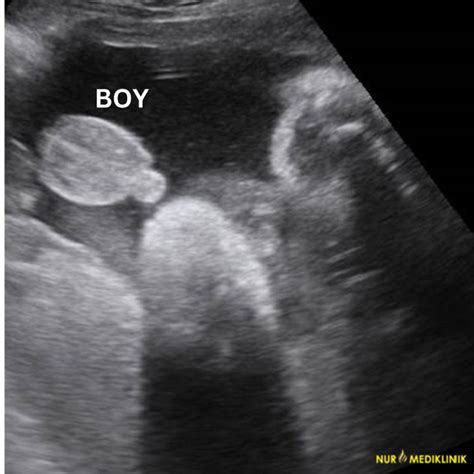

So, what exactly is a jantina baby scan ? Essentially, it’s a type of ultrasound used during pregnancy. The term ‘jantina’ isn’t a standard medical term you’ll find in textbooks, and it’s likely a colloquial or regional term used to refer to a specific type of scan, often associated with determining the baby’s gender. In most clinical settings, this kind of information is usually gathered during the anomaly scan or a dedicated ‘gender scan’. The primary purpose of any ultrasound scan during pregnancy is to monitor the baby’s growth and development, check for any potential issues, and provide reassurance to the parents. The jantina scan, therefore, falls under this umbrella, with a particular focus on visualizing the external genitalia to reveal the baby’s sex. It’s a moment filled with anticipation for many parents, eager to know if they’ll be welcoming a baby boy or a baby girl. The technology behind these scans uses sound waves to create an image of the baby on a screen, and it’s absolutely incredible to see your little one moving and growing. While the medical team will be assessing the baby’s health, for many, the highlight is catching that first glimpse of whether it’s team pink or team blue! It’s important to remember that while these scans are generally very accurate, there can be instances where the baby’s position makes it difficult to get a clear view, leading to uncertainty. But the thrill of potentially finding out the gender is what makes the jantina scan a highly anticipated event for most expecting families. We’ll delve deeper into the specifics of when you can get this information and what else you can expect from your scan experience.

The timing for a jantina baby scan is crucial, and it largely depends on when the baby’s sex organs become sufficiently developed to be visible on ultrasound. Generally, the earliest you might be able to get a reliable indication of your baby’s gender is around the 18 to 20-week anomaly scan . This is a standard mid-pregnancy ultrasound that most pregnant individuals undergo. During this comprehensive scan, the sonographer will check the baby’s anatomy thoroughly, including the development of all major organs and limbs. It’s during this detailed examination that they will also attempt to identify the baby’s sex by looking for external genitalia. However, it’s really important to understand that the 18-20 week scan’s primary purpose is not gender determination; it’s to assess the baby’s health and detect any potential abnormalities. Therefore, while gender information might be shared if it’s clear, it’s not guaranteed. If the sonographer can’t get a clear view due to the baby’s position or other factors, you might have to wait. Some clinics offer dedicated ‘gender scans’ or ‘sexing scans’ that can be performed a bit later, typically between 20 and 24 weeks of pregnancy . These scans are specifically focused on determining the baby’s sex and often provide clearer images as the baby is a bit bigger. However, even at this stage, the baby’s position can still play a role in the accuracy of the scan. It’s also worth noting that some private clinics might offer earlier scans, but the accuracy is generally lower before 18 weeks. So, for a reliable result, aiming for the 18-20 week anomaly scan or a dedicated scan between 20-24 weeks is your best bet, guys. Always chat with your healthcare provider or the scanning clinic about the best timing for your specific situation.

It’s totally normal to have a bunch of questions swirling around when it comes to finding out your baby’s gender via a jantina baby scan . Let’s tackle some of the most common ones, guys! One frequent question is: “How accurate are these scans?” Generally, ultrasound scans for gender determination are quite accurate, especially when performed between 20 and 24 weeks . Accuracy rates are often cited as being over 95%, sometimes even higher. However, remember that accuracy depends heavily on factors like the baby’s position, the equipment used, and the sonographer’s expertise. “Can I find out the gender before 18 weeks?” While some private clinics may offer earlier scans, the reliability is significantly lower. The fetal anatomy, particularly the genitalia, is usually not developed enough for clear identification before 18 weeks. Trying too early can lead to misidentification. “What if the sonographer can’t tell the gender?” This is quite common! As we’ve covered, the baby might be in an awkward position, or there might be other imaging challenges. In such cases, the sonographer might suggest rescheduling the scan or advise you to wait for your next routine appointment where it might be clearer. Don’t get discouraged; it just means your little one is playing coy! “Can the scan detect genetic abnormalities related to sex?” While the anomaly scan checks for physical development, it’s not primarily designed to detect specific genetic conditions related to sex chromosomes, although some abnormalities might be incidentally noted. For detailed genetic screening, specific tests like NIPT or amniocentesis are used. “Is a jantina scan medically necessary?” The scan commonly associated with the ‘jantina’ reveal is the 18-20 week anomaly scan, which is medically recommended for assessing fetal development and health. However, a scan solely for gender determination is usually considered elective or cosmetic. Always discuss the necessity and purpose of any scan with your healthcare provider. Understanding these common queries can help you feel more prepared and informed about your jantina baby scan experience, guys!